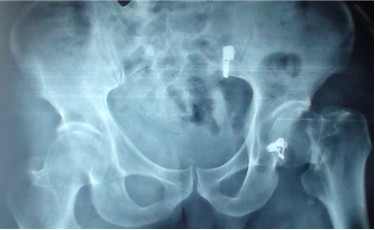

笔者对该事件进行了跟踪报道,该伤者被查出是左侧股骨颈骨折,郑州仁济医院已对其实施了股骨颈闭合复位术,用时50分钟,手术成功。现在一切良好,对于该伤者的病情,笔者会继续跟踪报道。

术中 术后的片子